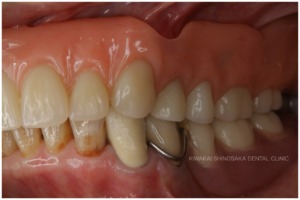

インプラント治療は希望されず、自由診療による総義歯(BPS義歯)のプランを選択されましたので、壊れにくく、吸着の良い精密技工義歯治療を行いました。

義歯装着後は痛みもなく、現在までほぼ無調整で約7年間快適にお過ごしいただいています。

保険内の治療では、素材や精度に制限があるため、義歯の適合性に差が生じやすくなりますが、自由診療内での治療であれば、より高い適合性と審美性を重視した義歯の作製が可能となります。精度の良い義歯は痛みや違和感などの変化が起きにくく、安定性が見込めるため、インプラントオーバーデンチャーを希望された際にもご提案させていただいております。